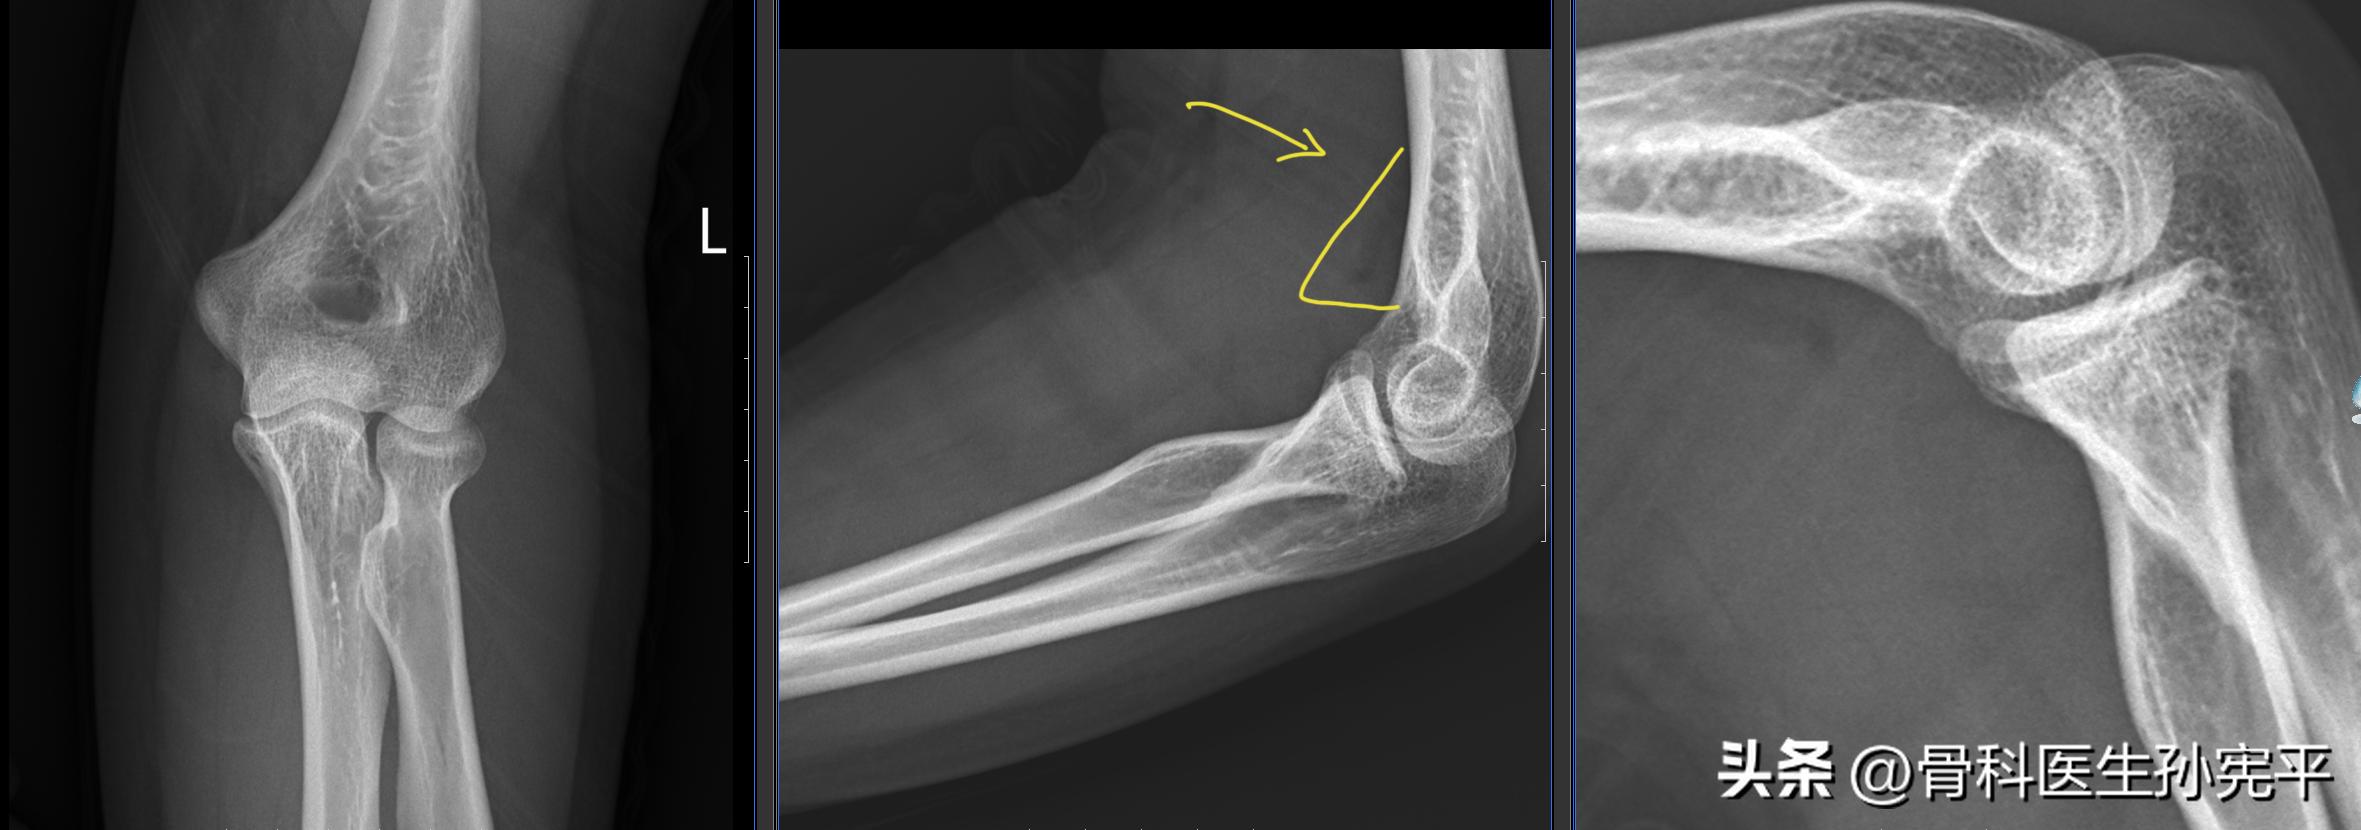

病例5:摔倒后左肘关节疼痛3小时。

肘关节“船帆征”

阅片未见明显骨折征象,但可见左肘关节前侧脂肪垫征“船帆征”改变。进一步查肘关节CT,结果如下:

左桡骨小头骨折

脂肪垫征又称作船帆征或八字征,当肘关节损伤时,关节腔内积液或出血,关节囊肿胀,在X线片上可能会出现肘前/后脂肪垫影。细微的软组织表现对肘部损伤十分重要,不应疏忽,脂肪垫征可见于肱骨髁上骨折、外侧髁骨折、桡骨小头骨折等。虽然脂肪垫征≠骨折,但骨折概率明显增大,对于有外伤史的病人可能X线片未见明显骨折征象,但对于出现船帆征或八字征的病人要定期复诊、复查,必要时行肘关节CT或核磁检查,进一步明确是否合并骨折。